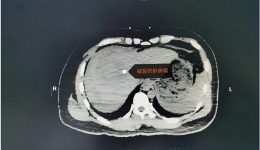

【健康科普】肝癌的预防、早期诊断及治疗